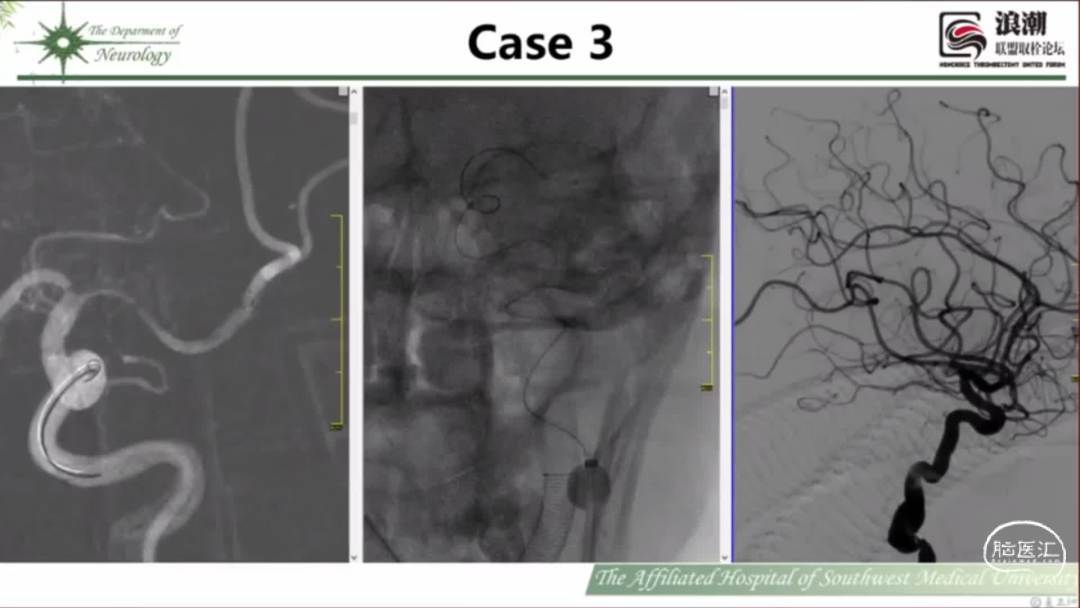

中间导管平衡了柔顺性和支撑性,能够在迂曲的血管解剖结构中推进,提供远端支持,为其他介入材料的进入提供支持。部分用于抽吸取栓。

本期为大家特别分享:西南医科大学附属医院袁正洲教授的精彩会议内容《山舞银蛇——银蛇颅内支持导管使用分享》,欢迎大家阅读和分享!